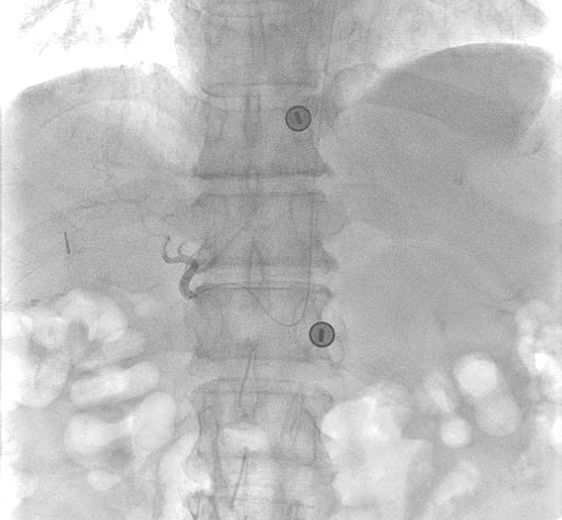

近日,医学影像科刘强教授团队与普通外科陆宏伟教授团队通力合作,成功为一名肝癌患者实施了“无鞘微导管技术”的介入治疗,完成了我院首例经桡无鞘微导管舒适HAIC(肝动脉化疗灌注术)。该技术为一名肝癌患者实现了真正意义上的超微创精准介入治疗,术中血管创口仅约0.8mm,患者术后即可步行返回病房,真正做到了创伤小、恢复快,显著提升了治疗的安全性与舒适度,获得了患者及家属的高度认可。

相比传统经股动脉路径HAIC,经桡无鞘微导管舒适HAIC具备三大优势:一是创伤更小——摒弃传统鞘管,血管创口仅为0.50-0.87mm,创口面积较传统方式减少80%以上;二是舒适度更高——患者术后即可下地活动,治疗期间无需长期卧床,生活自理能力得到保障;三是恢复更快——术后仅需压迫止血约2小时,相较于传统术后需卧床制动6-24小时,大大缩短了康复周期。这标志着HAIC治疗向更人性化、更微创的方向迈出关键一步。